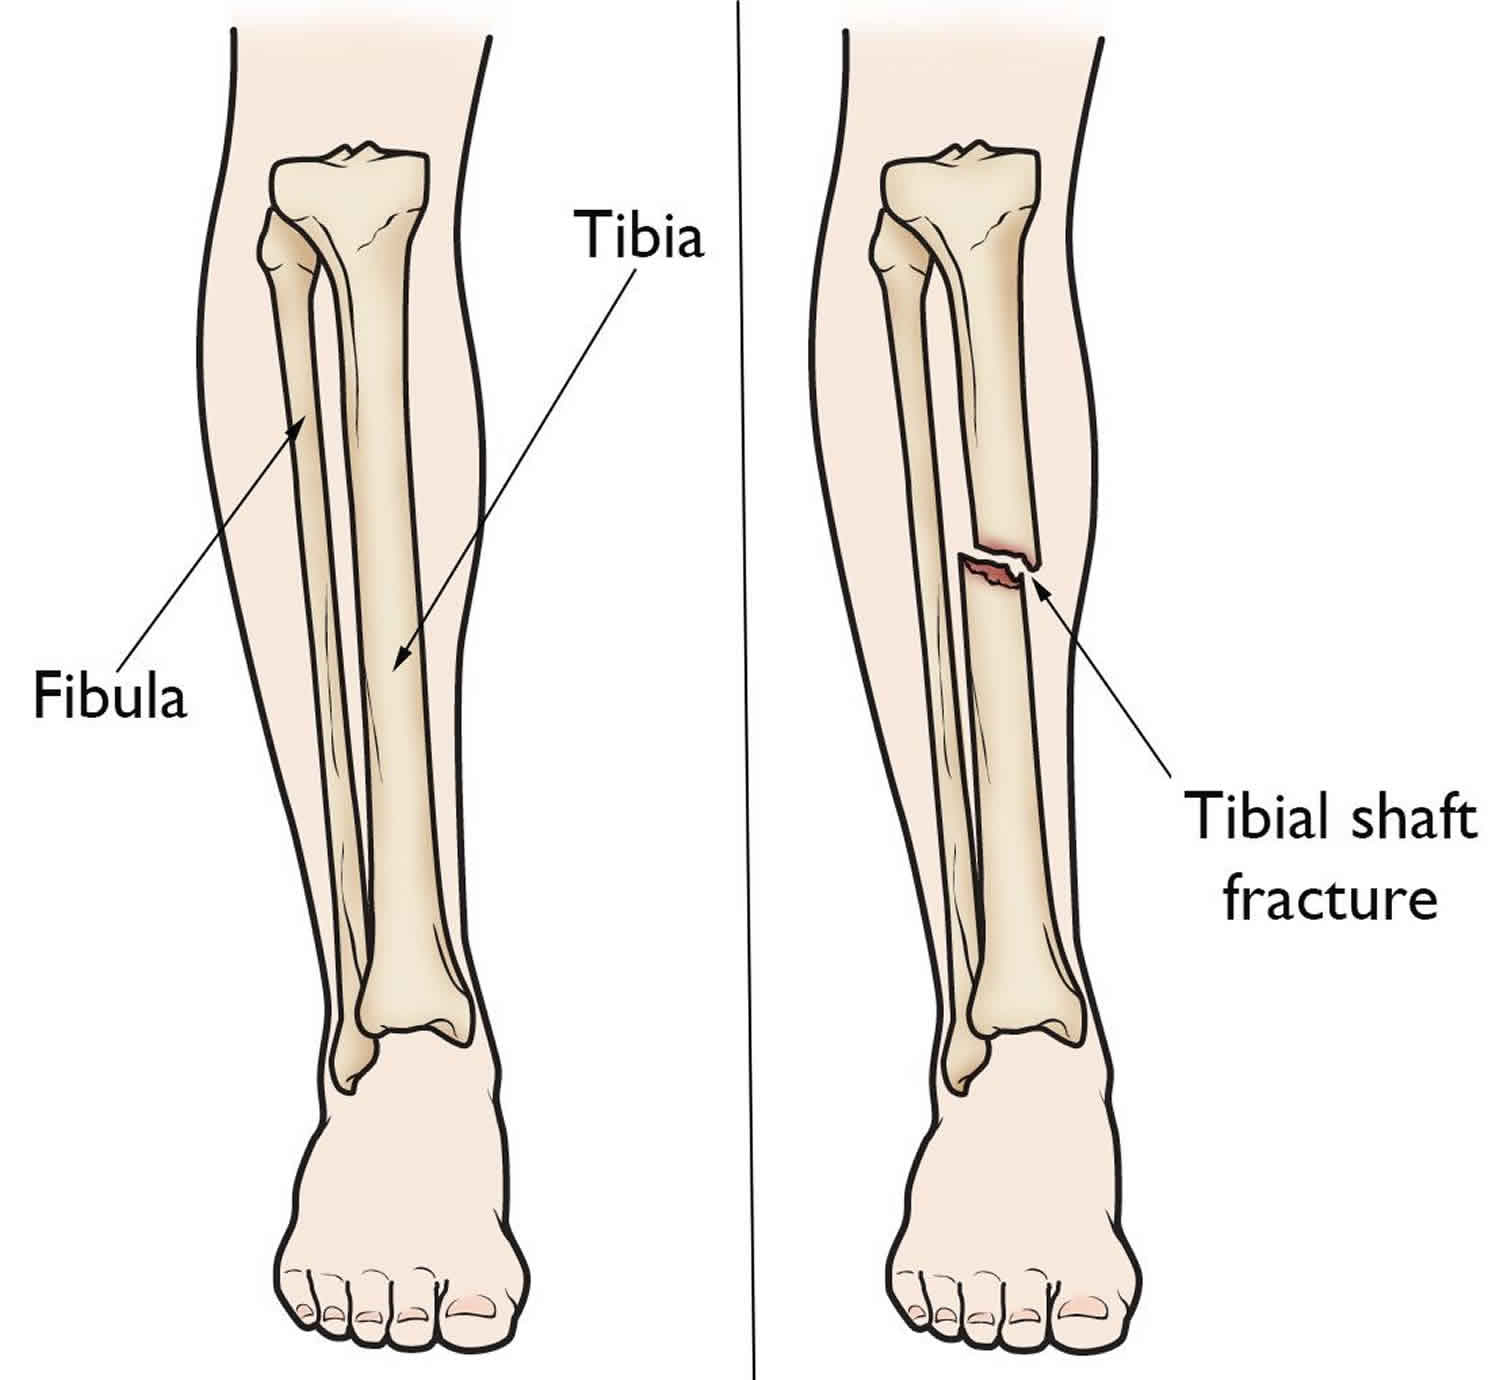

Tibial shaft fracture causes, types, symptoms, diagnosis, treatment …

Closed Tibia or Fibula Fracture|Causes|Symptoms|Treatment|Recovery

Tibial and Fibular Fracture – TrialExhibits Inc.

Tibia and fibula, shaft: simple fracture, oblique | Musculoskeletal Key

Tibia and fibula, shaft—introduction | Musculoskeletal Key

Fractures of the Shaft of the Tibia and Fibula – TeachMe Orthopedics